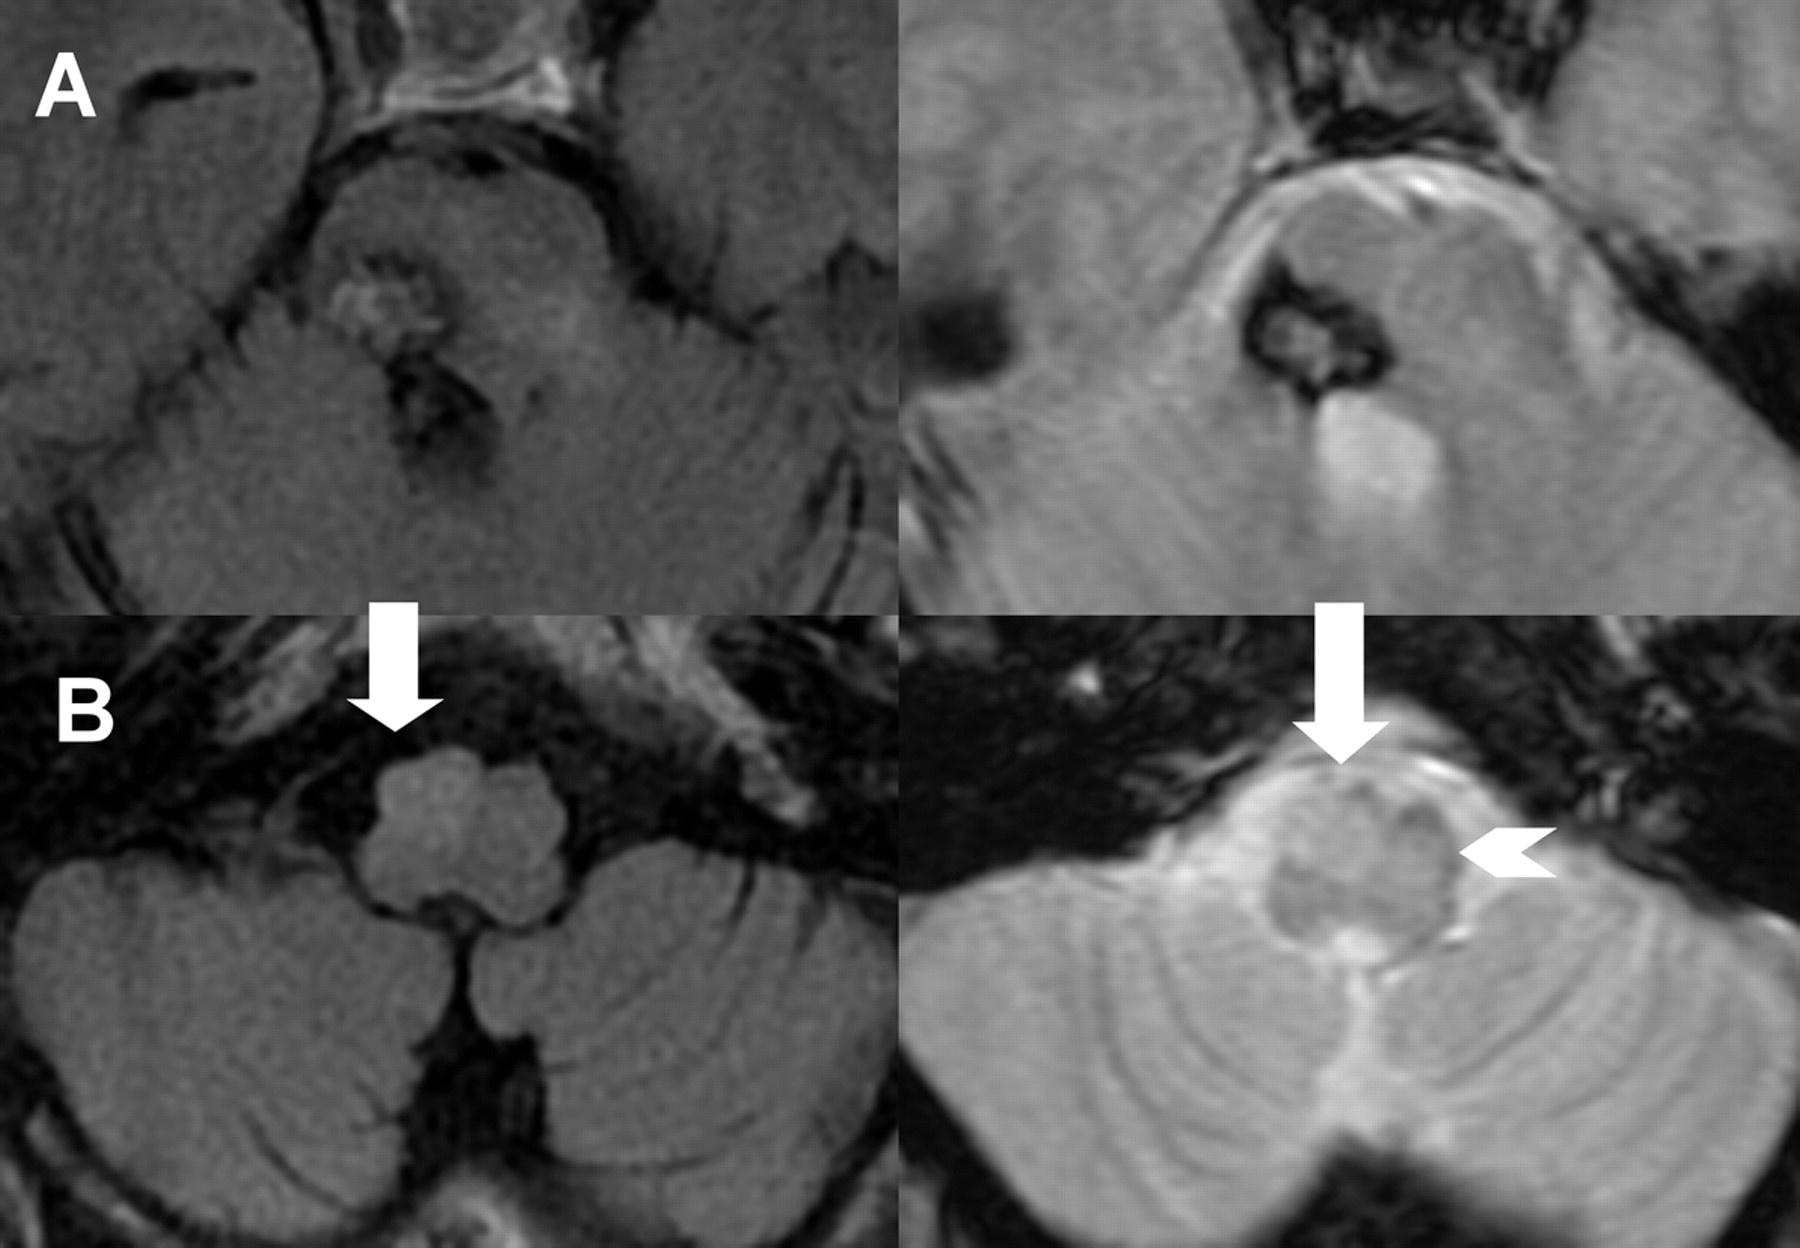

49岁的坐在轮椅上的人是呈现左hemi-paretic,构音障碍的,diplopic后脑干出血。几个月后,他开发了一种逐步禁用左臂震颤。检查显示倾斜偏差,左hemipare-sis,左偏身麻木,躯干的运动失调,姿势和动作近端左臂震颤(视频)。脑部MRI表现出对脑干上部和畸形的同侧下橄榄核二级放大中央盖的呼吸道病变(图)。小脑肢体震颤与对侧的肥厚性劣质橄榄油,类似于二级腭震颤,1延迟性的数周或数月后损伤可能是由于补偿运动系统的变化。2